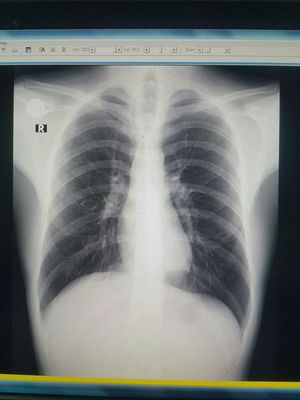

Dx???